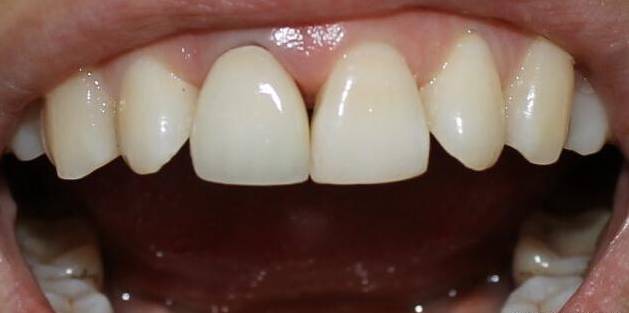

原因二:龋齿(蛀牙)

还有一种可能就是龋坏,即虫牙,也会变黑。这种情况一般去补牙就行了,补牙前都会把龋坏先清理干净,再做充填。早期蛀牙只需要填牙就可以了,到了中后期的蛀牙就需要根管治疗或者拔除了。

4、补牙修复:如果出现蛀牙情况,需及时前往正规医院进行全面检查并补牙修复。尽量不要用刚补好的牙去咀嚼食物,以免损坏或脱落。